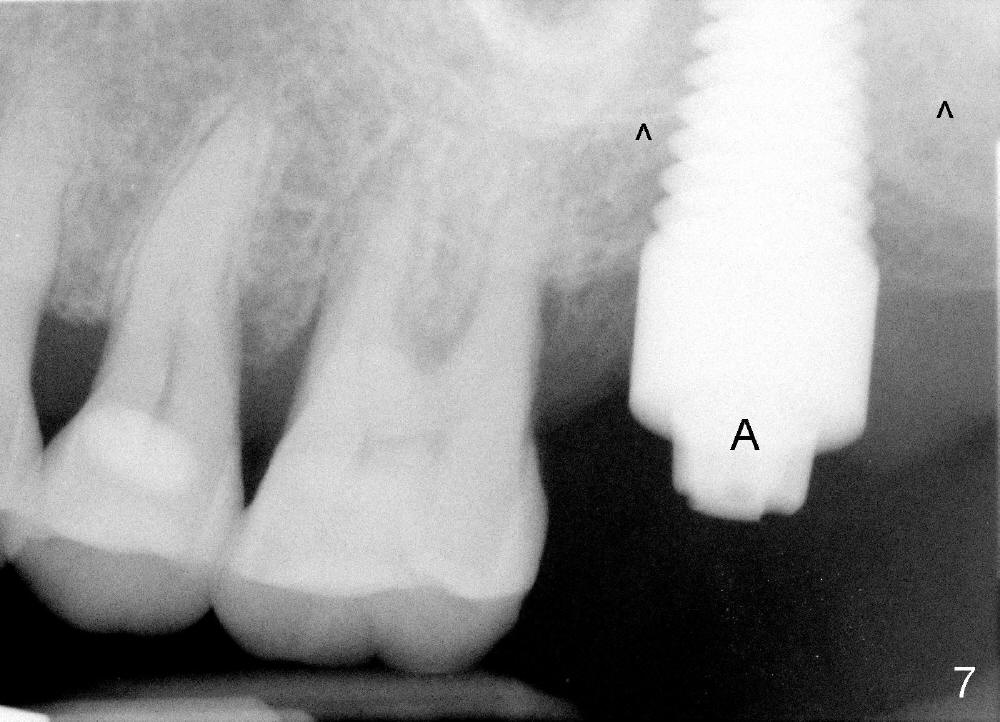

Next time she returns 4.5 months postop, bone looks normal around the implant (Fig.7), whereas the buccal gingival recession appears to get worse with 1-2 implant thread exposure (Fig.8 >). To avoid this complication, the initial osteotomy should be placed as palatal as possible; when the implant is placed with gingival recession (Fig.5), soft tissue graft should be performed. The implant should be smaller.